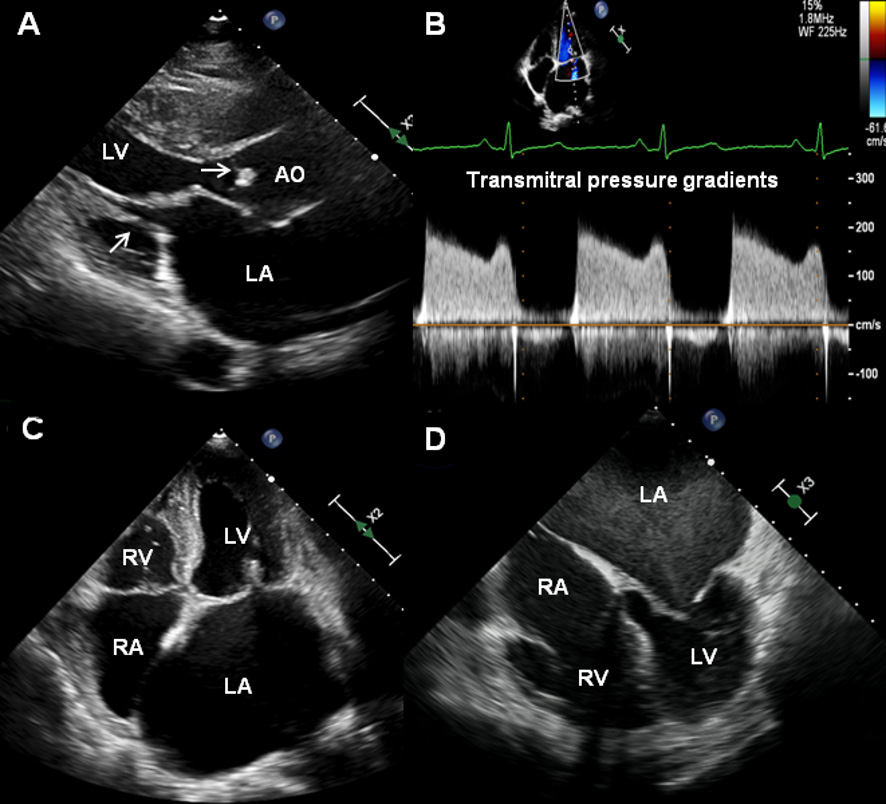

研究人员选择了经临床和超声心动图诊断为RHD的患者。在受试者入组时进行了结构化的临床和神经学评估,以确定卒中的病因和分类。

该研究共纳入了515例患者,其中女性438例(85%),年龄为46±12岁。最常见的瓣膜病变是混合二尖瓣病变(80%)。入组时,92例患者(18%)既往有过卒中,最常见的是前循环梗死(72%)。在平均3.9年的随访中,27名患者(5.2%)发生脑卒中,总发生率为每100名患者每年1.47人。Cox模型预测卒中的因素包括既往卒中(校正后HR为5.395, 95%CI为2.272-12.811)、年龄(HR为1.591, 95%CI为1.116-2.269)和基线时房颤(HR为2.945, 95%CI为1.083-8.007)。通过将死亡作为竞争风险,AF对卒中风险的影响有所减弱(HR为2.287, 95%CI为0.962-5.441)。